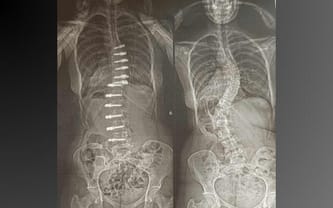

Operacja kręgosłupa to ostatnia szansa, aby Martyna mogła pozbyć się bólu! Pomóż!

Cel zbiórki: Operacja kręgosłupa w klinice w Mediolanie

Skolioza idiopatyczna

22 lipca przeszłam operację kręgosłupa w Mediolanie.

Operacja się udała, efekt jest naprawdę dobry, lepszy niż mogłabym sądzić! Okres rekonwalescencji jest bardzo trudny, ale nie poddaję się.

Wierzę, że już niedługo zapomnę o bólu i zacznę się cieszyć moim nowym, prostym i elastycznym kręgosłupem. Jak tylko poczuję się lepiej, zaczynam też intensywną rehabilitację.